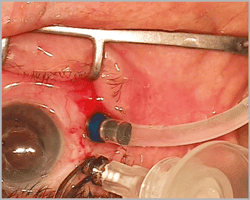

- M09 9002 : Akkan VFE System 19g x 3mm (1.10mm x 3mm) for 20g and 23g

- V02-001 : Akkan VFE System 19g x 3mm (1.10mm x 3mm) for 20g and 23g

Akkan VFE Sistemi 20g ve 23g trokar sistemi ile kullanılır. VFE sistemi aspirasyon sırasında silikon yağının yayılmasını engeller. Göz içine girmeden silikonun aspirasyonunu sağlar.

MMT Meran Medikal Teknoloji Koll. Şti. tarafından iki farklı marka altında aynı kalitede ve aynı ürün olarak üretilir. Steril ve tek kullanımlıktır.